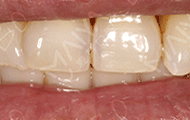

2017年12月24日 生活又开始多姿多彩

今天来医院进行复诊,医生说我恢复的特别好。不得不感慨一下,虽然烤瓷牙、活动假牙比种植牙便宜,但是咀嚼力和使用性都比不上种植牙,不愧是“人类的第三副牙齿”。

现在我出门应酬,他们都不相信我的前牙曾经掉过,还以为是真牙,我身边也有缺牙的朋友,自从说完我的种牙经历,他们说不能拖了,早种牙早受益。现在我可以正常的进行饮食了,像排骨、大闸蟹、小龙虾这类的美食,随时品尝,而且苹果、梨这些的“硬”水果也是想吃就吃,生活又开始多姿多彩了。